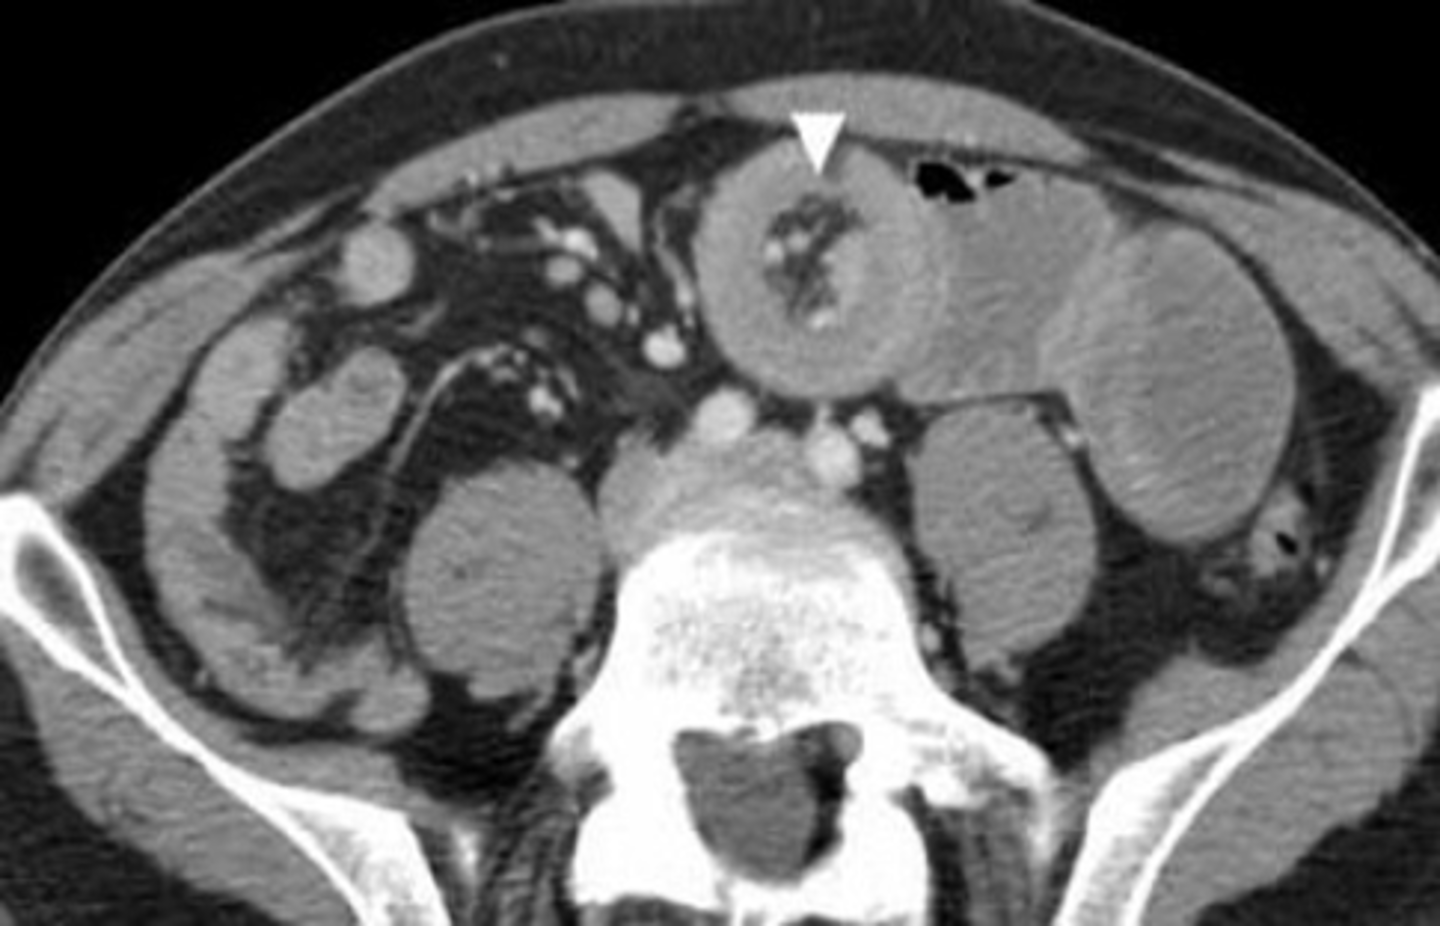

ENLARGED KIDNEY

Organomegaly or soft tissue masses - can be dx either by:

1) visualizing the edge of the mass if there is fat or air surrounding it

2) displacement of bowel

A:

WHITE ARROWS: soft tissue mass on LUQ

BLACK ARROW: displacement of bowels to the right

B: CT of the same patient

WHITE ARROW: large renal cyst arising from left kidney, displacing it and surrounding bowel.

BLACK ARROW: left kidney.

S: spleen, compressed by cyst.